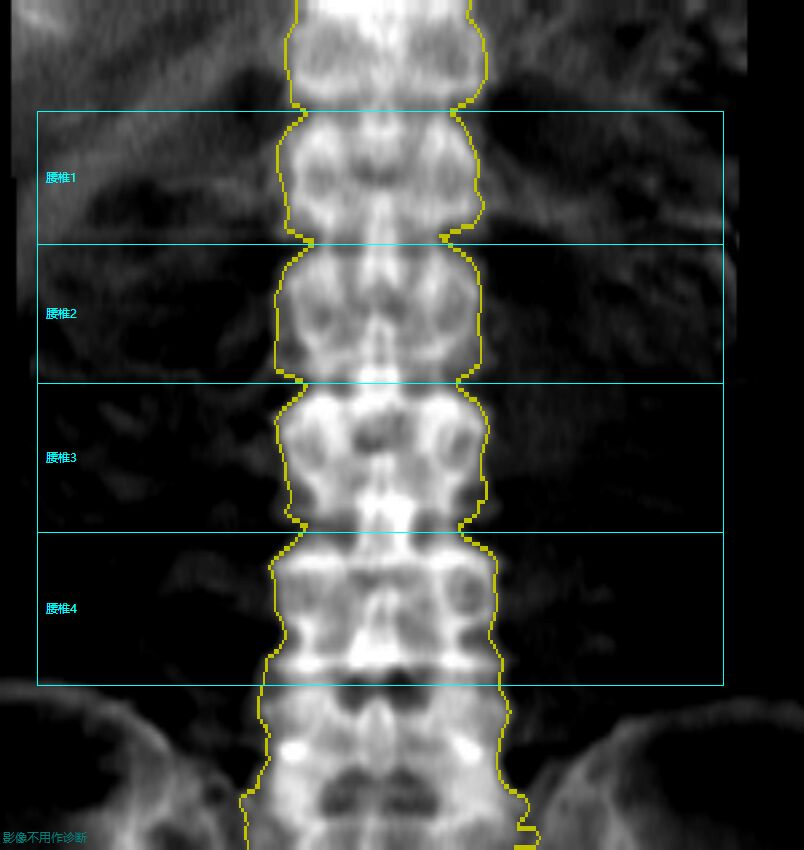

现代社会中,骨骼疾病特别是骨质疏松等骨代谢性疾病发生率日渐上升。为加强对骨代谢疾病的临床基础研究,我院引进GE LUNAR是GE医疗推出的骨密度检测设备系列,主要采用双能X线吸收法(DXA)技术,用于骨质疏松症的诊断和骨密度评估。其代表型号如Prodigy、iDXA等,核心优势在于辐射剂量极低(仅为胸片的1/100)、检测精度高,支持全身骨密度测量及肌肉脂肪分析,广泛应用于绝经后妇女、老年男性等骨质疏松高危人群的筛查与随访。

GE LUNAR的Prodigy和iDXA作为双能数字化X线骨密度测量的尖端设备,检测准确性较高,其测量精准,是精度记录的保持者(精度达0.6%),且唯一采用中华医学会建立的中国大陆人骨密度参考数据库,有助于更准确的诊断。